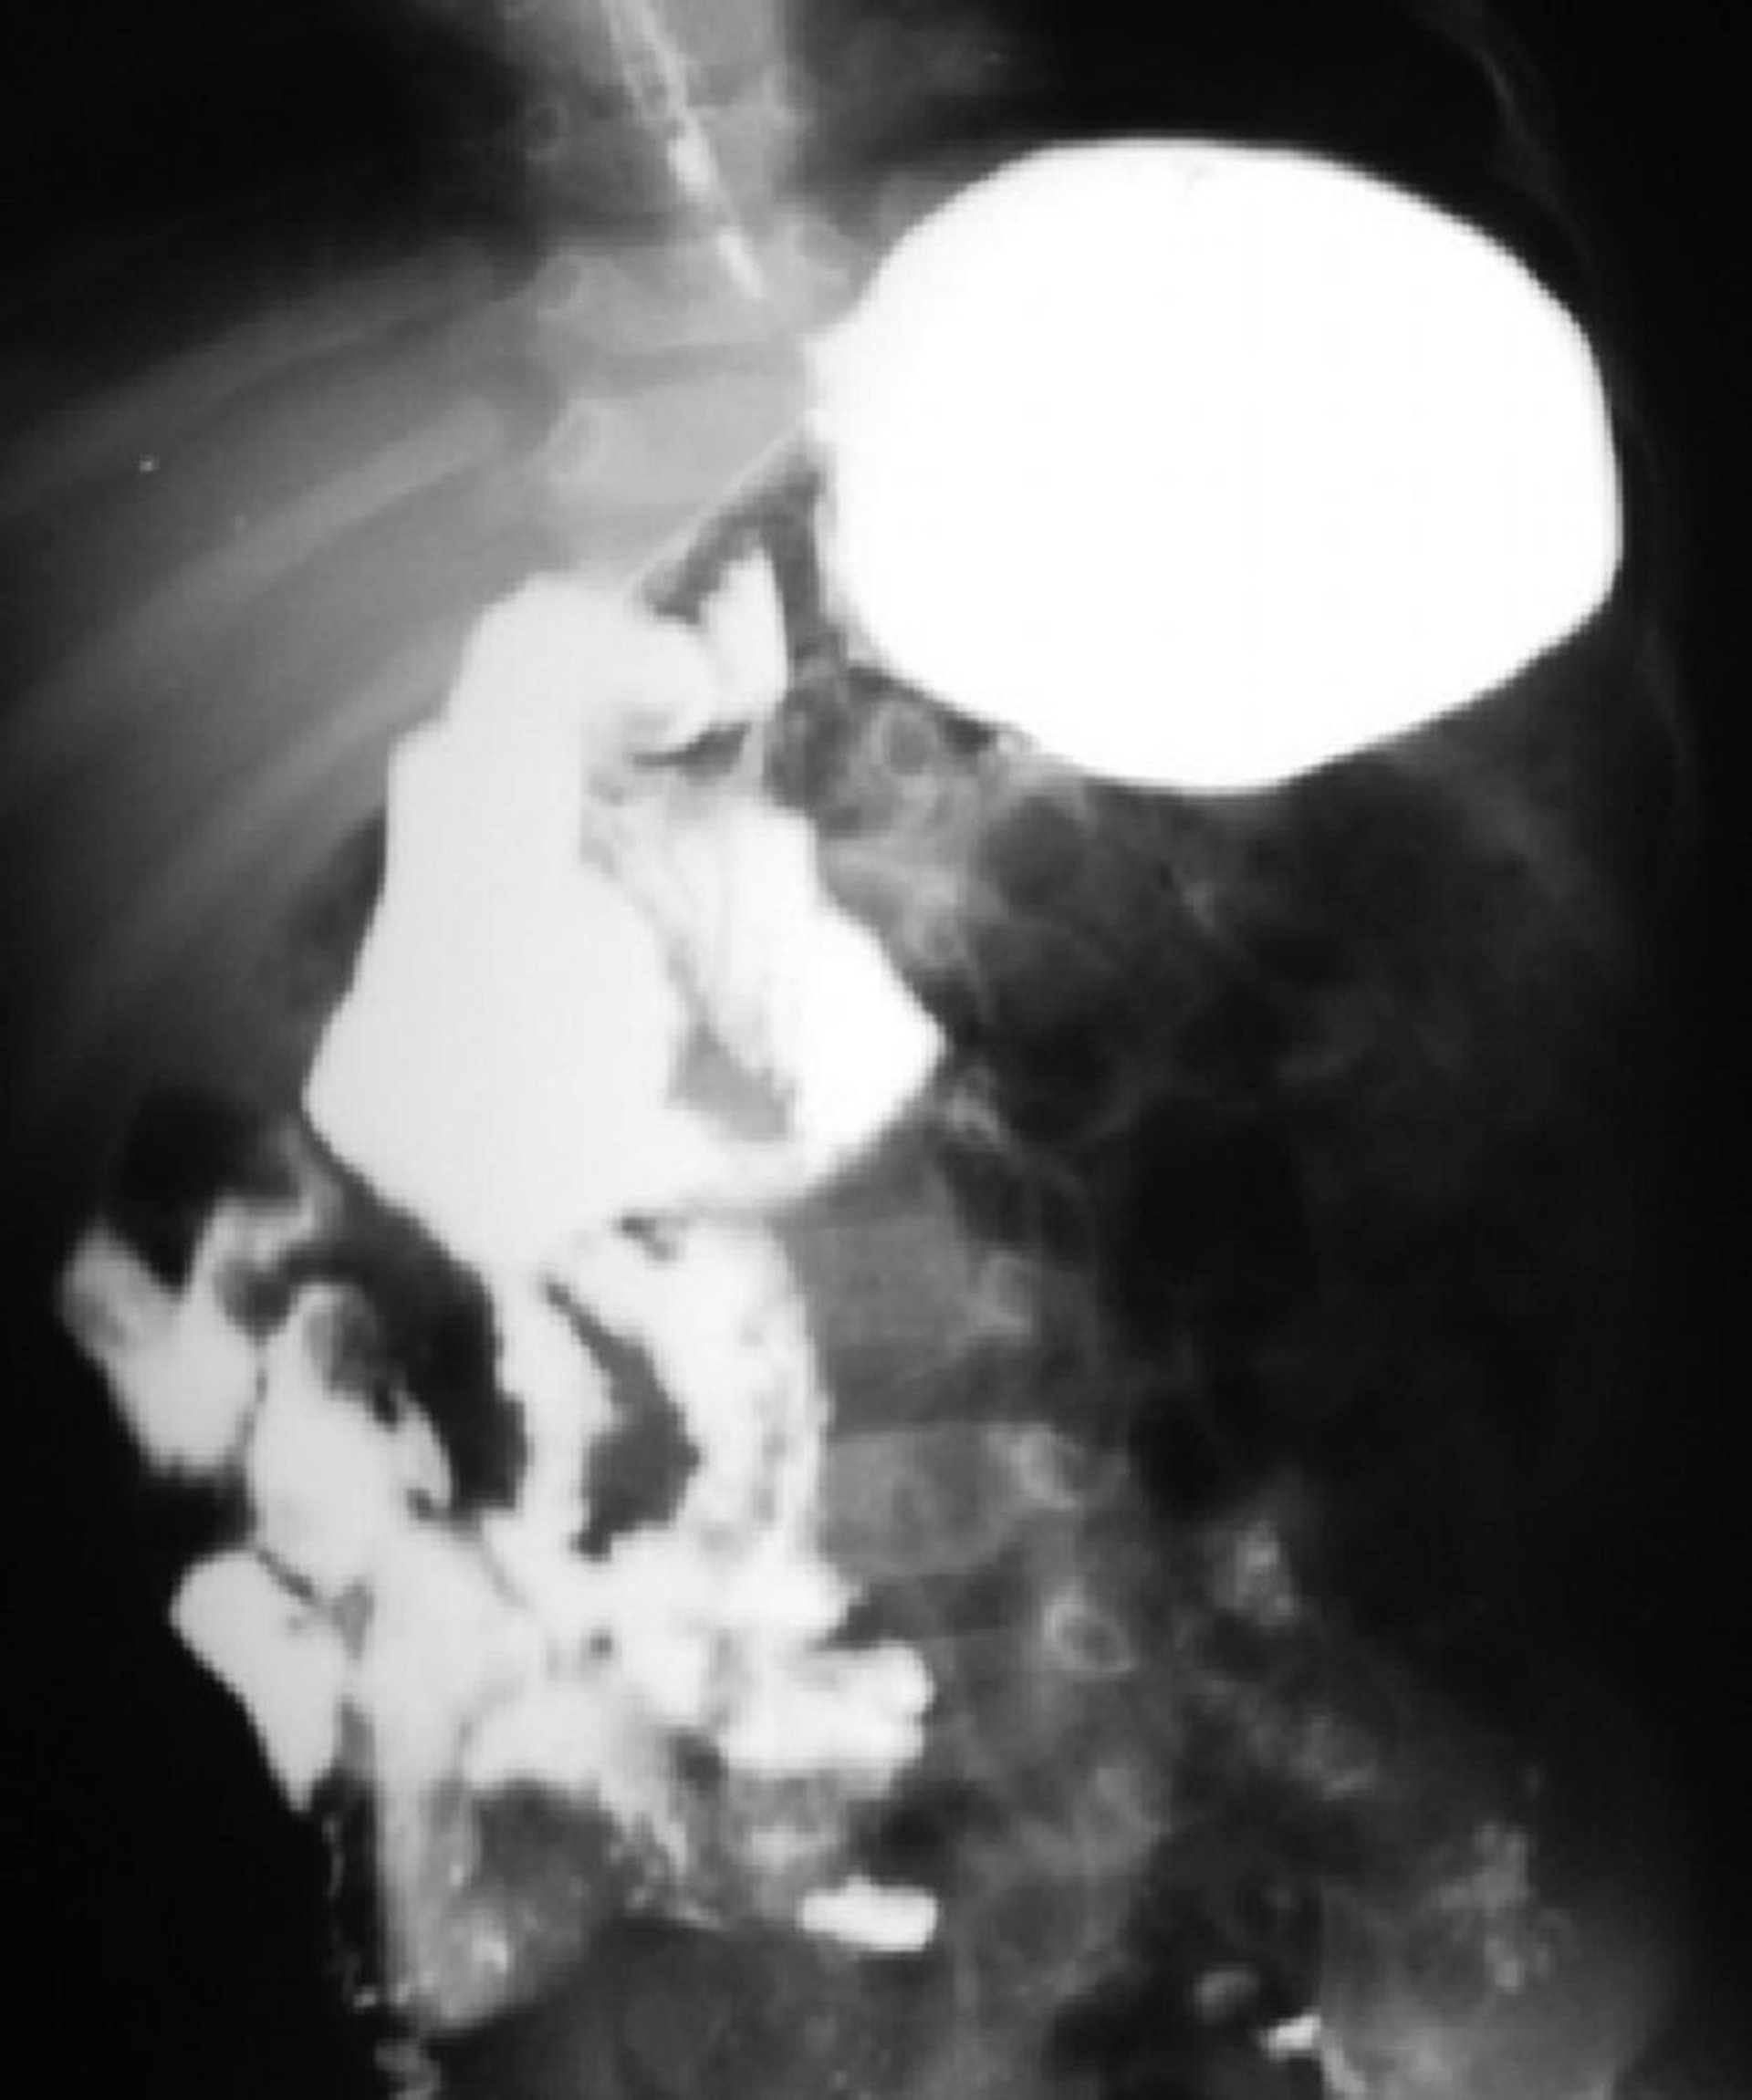

この消化管造影像には腸管の回転異常が認められる。十二指腸空腸移行部が脊椎の右外側にあり,小腸の大半が右側にある。